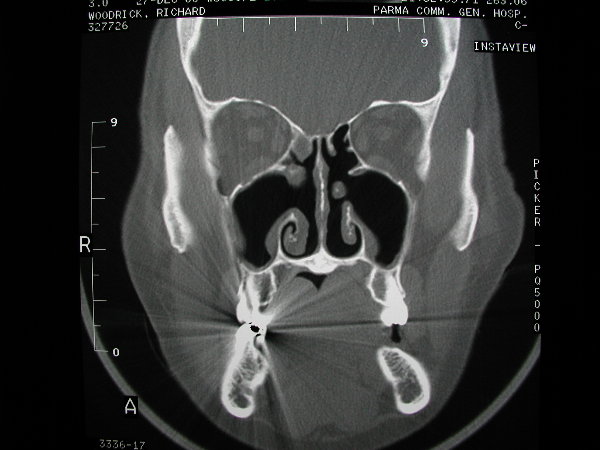

The patient above had previous sinus surgery.  Maxillary antrostomies were created which did not incorporate the patient's natural maxillary antrostomies, hence his symptoms persisted.  Careful evaluation of his CTs and appropriate connection of his natural to iatrogenic ostia led to recovery.